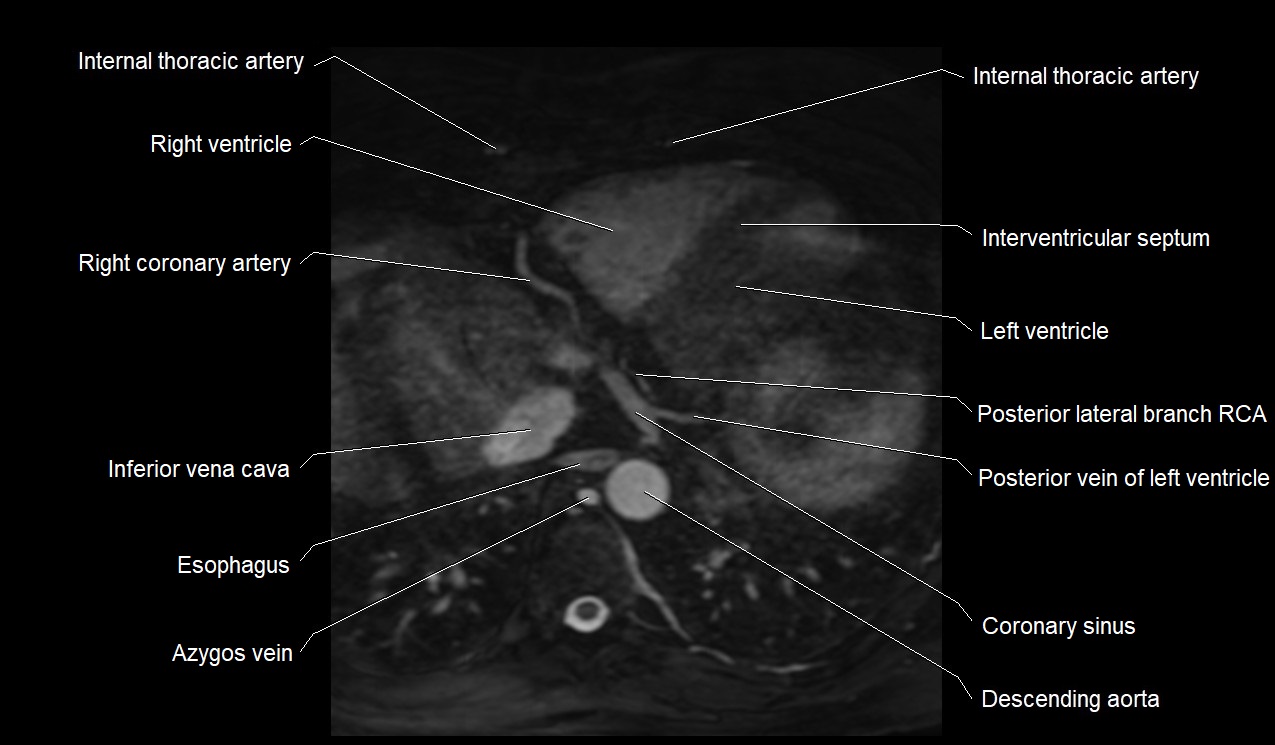

MRI image